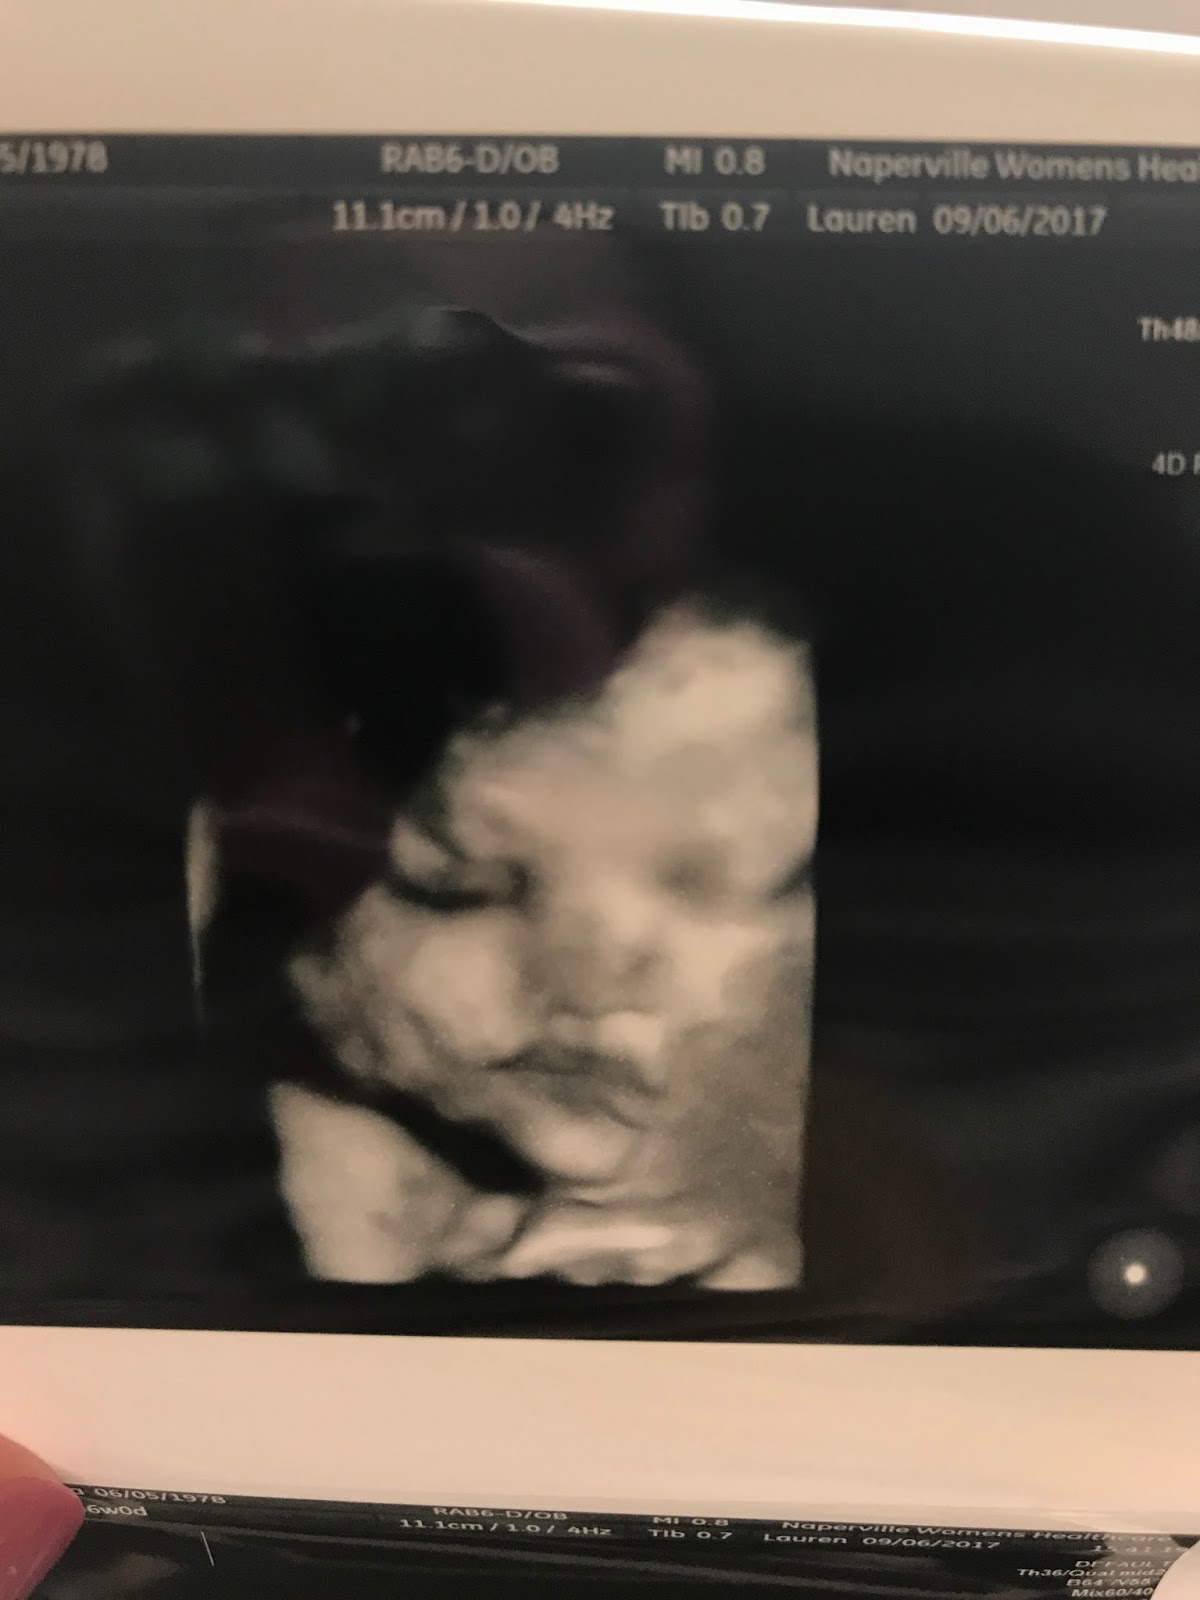

This is a 3D ultrasound of her face. They checked all of her organs today and everything looks normal. That's her little hand up by her face, just like the

last ultrasound.